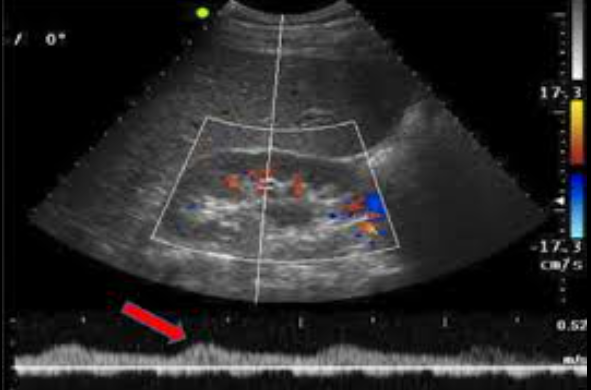

Hydro can cause an RI above..

0.7

Sono findings of RAS (3)

- thickening and calcification of renal artery

- renal to aorta ratio above 3.5

- tardus parvus waveform